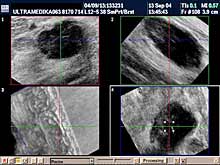

- ako postoji promena i mikrokalcifikacija obavezna je primena: 3D Sono CT i 3D CPA i Broad

band-CD i CPD,

- ako postoji sumnja na zloćudnu promenu pored navedenog

potrebna je procena morfologije i krvnih sudova regionalnih limfnih

žlezda.

Primenjena tehnika:

- 2D broad band,

- Sono

CT,

- XRes,

- 3D Sono CT,

- Broad band - CD i CPD,

- 3D CPA.